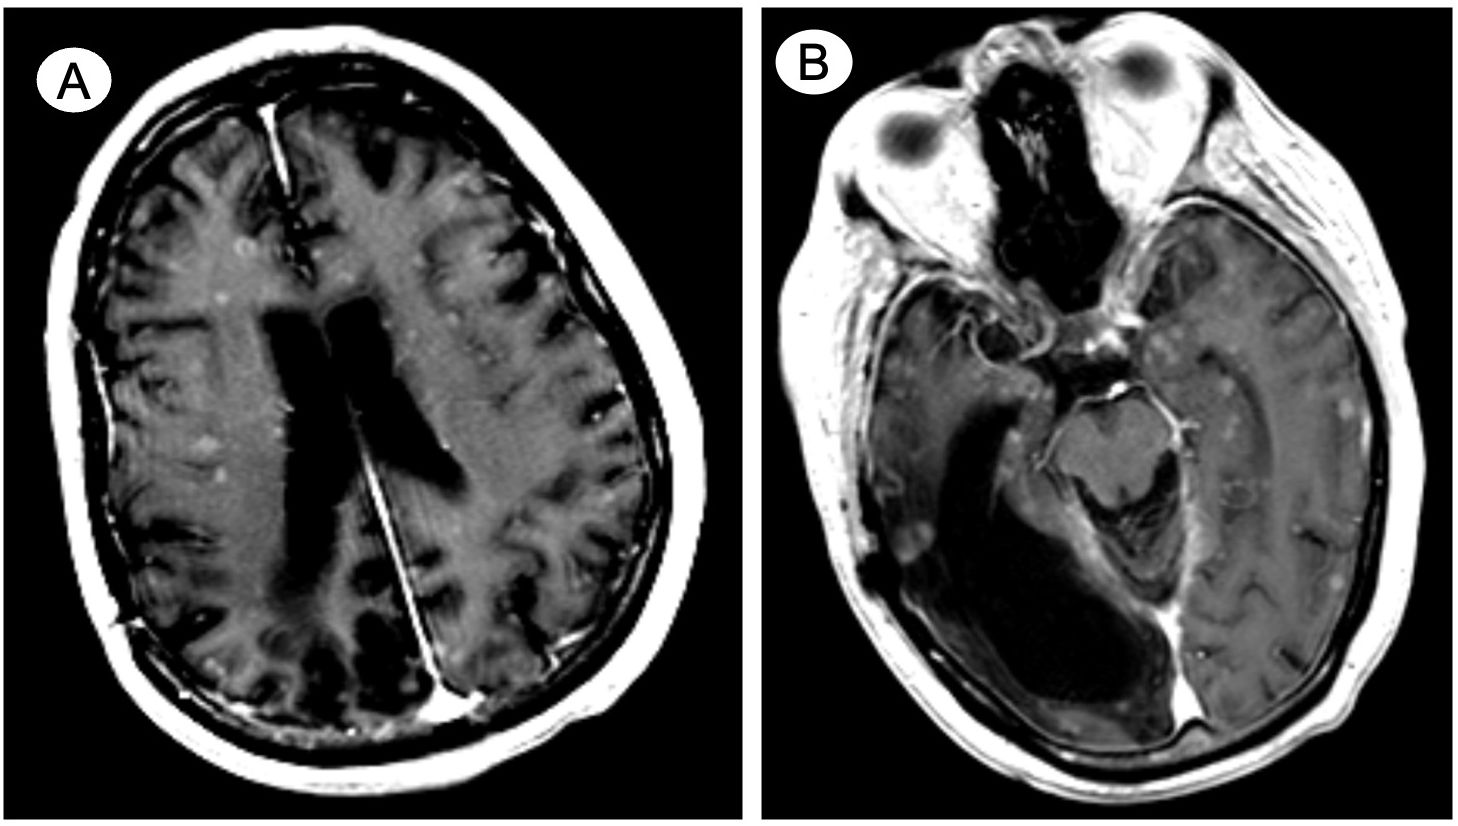

Introduction: Miliary brain metastasis (MM), consisting of innumerable miliary lesions in perivascular location, is a rare disease entity with an estimated incidence of 3.8% among patients with brain metastasis (BM). Similarly, with an approximated incidence of less than 2%, prostate cancer (PC)-related BM is also an infrequent presentation; however, it is more common in patients with neuroendocrine differentiation. To the best of our knowledge, one other case of MM secondary to PC has been reported. This case report discusses two additional cases of PC-related MM, a condition otherwise predominately observed secondary to pulmonary adenocarcinoma. Case Presentations: The first case describes a patient in his 60s known for metastatic PC with suspected neuroendocrine differentiation presenting with musculoskeletal pain, lethargy, and status epilepticus. Contrast-enhanced computer tomography (CT) angiogram and magnetic resonance imaging (MRI) of the head and neck revealed diffuse and innumerable foci in the cerebral hemispheres, brainstem, and cerebellum. The second case discusses a similarly aged male with biopsy-proven de novo mixed adenocarcinoma/small cell neuroendocrine PC and symptoms consisting of significant weakness, aphasia, confusion, and decreased level of consciousness. Non-contrast-enhanced CT imaging of the brain did not reveal MM; however, a follow-up contrast-enhanced MRI detailed miliary lesions in the cortex, white matter, deep gray nuclei, brainstem, and cerebellum. Both patients expired within a couple of weeks from admission. Conclusion: Given its rarity, notably in patients with PC, there are no specific and established diagnostic criteria for MM, a condition with ominous prognosis seemingly related to neuroendocrine differentiation in men with PC.